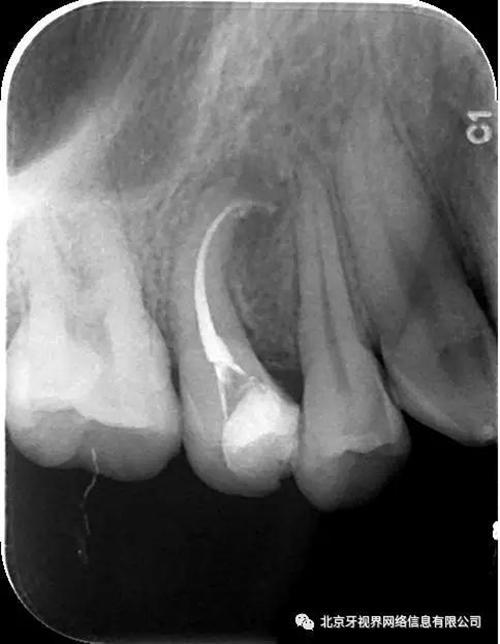

2次復(fù)診常規(guī)根備加根充(AH-plus糊劑加牙膠尖根充)

討論:1.術(shù)前評估尤為重要,它能讓我們更清晰的了解病變大小,根管的彎曲程度,以及操作的難點(diǎn)。